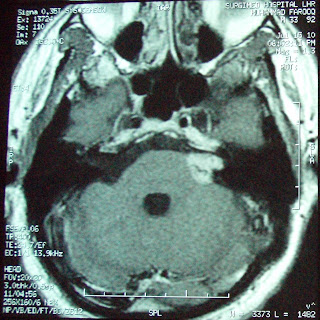

This 32 years old gentleman from Lahore was a diagnosed case of left Acoustic Schwannoma.He presented with progressive left hearing loss since 10th June 09, left hemi facial numbness, mild headache , loss of taste and occasional imbalance since 20 days. Clinical examination revealed left hemi facial hypoesthesia and poor corneal reflex. MRI shows heterogeneously enhancing mass in left CPA. He was treated with marginal dose of 12.5 Gy at 50% isodose line to the target volume of 9.0 cc. Multiple isocenters with 14,  8 and 4 mm collimators were used in APS mode. He was discharged on tapering doses of Dexamethasone and advised for follow up images after 6 months.

F.up at one year shows 80% reduction in Tumor.